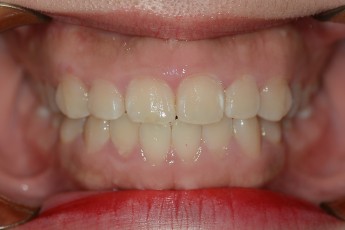

BEFORE & AFTER

- 급속부분교정